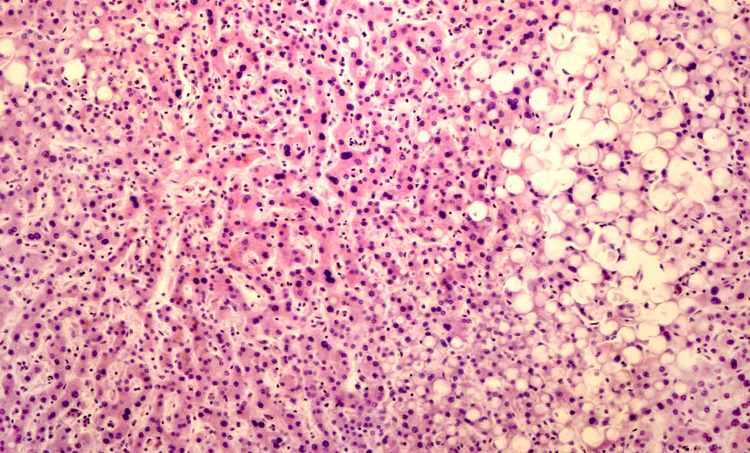

De non-alcoholisch vervette lever is een wereldwijd snelgroeiende ziekte, gelinkt aan obesitas, diabetes mellitus type 2 en metabool syndroom. Het is een steeds verdergaande vervetting van de lever met een steeds ernstiger vorm van leverlijden tot gevolg.

De gevoeligheid voor het ontwikkelen van leverlijden is van verschillenden factoren afhankelijk. Naast infectieziekten van de lever en alcoholisme worden momenteel vooral leefstijl-gerelateerde factoren zoals insulineresistentie (IR), de kwaliteit van het darmmicrobioom, overgewicht en het metabool syndroom gekoppeld aan het ontwikkelen van leverlijden.

In een artikel over de ontwikkeling van de pathogenese tot hepatosteatose worden verschillende paden genoemd in wat de zogenaamde multi-hit hypothese heet.2 Figuur 1 laat het mechanisme zien van het ontstaan van leverfibrose; daarboven in kolommen een aantal kruiden die de stappen kunnen remmen.

De verschillende oorzaken die genoemd worden in de pathogenese van MAFLD2,4 zijn genetische predispositie5, insulineresistentie, verstoorde vetstofwisseling, darmdysbiose, ontstekingsreacties in vetweefsel en lever, en epigenetische factoren.